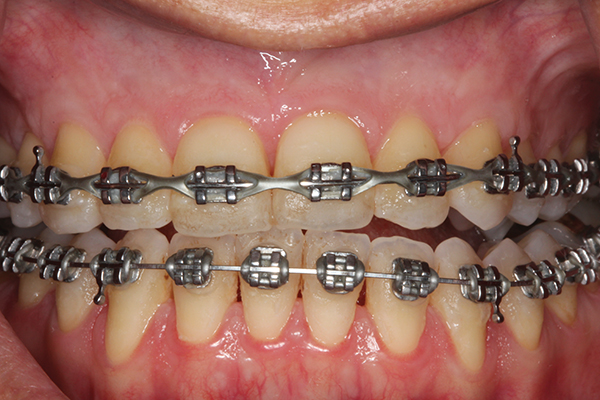

Fig 1. Preoperative SFOT. No loss of attachment, but thin dentoalveolar bone phenotype noted clinically.

Figure 1